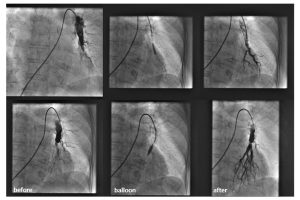

Balonska-angioplastika-plućne-arterije2 by croatiaweek August 10, 2025 in Sign up to receive the Croatia Week Newsletter